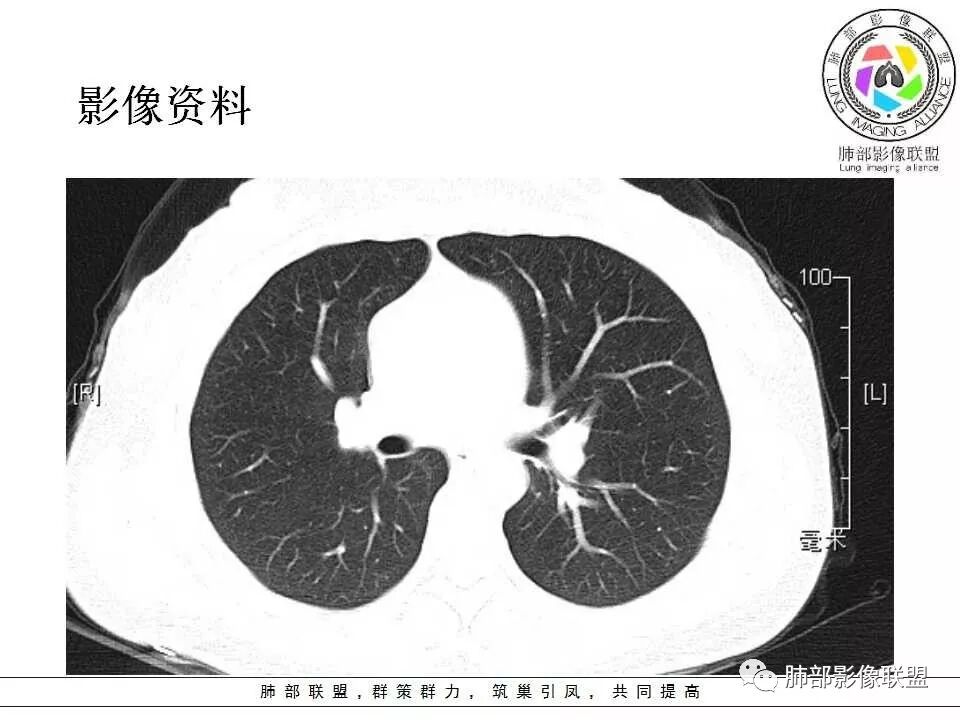

左肺病灶与支气管关系密切,类癌粘膜下生长,支气管略变窄,支气管外病变较大,符合冰山征表现,一年内有增长,考虑类癌,鉴别PSP,建议薄层重建。

左肺上叶后段紧贴斜裂结节影,支气管通畅,斜裂无移位,说明病灶来源斜裂可能,强化密度均匀,边缘清晰,考虑良性病变,PSP可能性大,鉴别CD。

青年女性,左肺门占位。定位:跨叶间裂,下叶邻近支气管推压,考虑肺外病变。影像表现:血管贴边,边缘光滑,强化均匀,考虑良性病变,PSP可能大,鉴别CD。

青年女性,一年前发现肺结节,复查有增大,未见近期片对比,定位:左肺上叶左肺门旁见实性类圆形结节,边界清晰光整,有部分分叶征,增强有均匀强化,与左上叶后段支气管关系不好判断,左上叶后段支气管未显示,堵塞?狭窄?需冠矢状面看看,定性:常规考虑良性或低度恶性肿瘤,典型的类癌或硬化性肺细胞瘤psp可能,神经源性或神经内分泌肿瘤、巨淋巴结增生症CD不除外,转移瘤、孤立性纤维瘤待排,建议HRCT或支气管镜检查。

年轻女性,左肺门区占位,斜裂推移未跨叶,类圆形,增强扫描明显强化,和支气管关系显示不是太清楚,感觉关系不是太密切,未见阻塞性炎症,一年后有长大,首先考虑PSP,鉴别类癌,SFT。

3.1单发型CD的肺部表现

单发型CD多为透明血管型,所以明显强化和中央分枝状钙化具有特征性。在CT上表现圆形或类圆形软组织密度影,伴或不伴周围淋巴结增生,体积一般较大,边缘光整,病灶中央的弧形、线样、分枝样及枯枝样钙化(因为肿块内增生的血管组织玻璃样变或退变后钙盐沉积,故多呈血管样铸型的分支状或枯枝状);透明血管型因为其内血供丰富,周围可见粗大的供血动脉,在多期扫描动脉早期明显强化,强化程度与大血管相仿,又由于病灶内血管壁玻璃样变或纤维化及内皮细胞过度增生致血管腔狭窄,对比剂退出减慢,故延迟扫描扫描仍可持续强化,呈“早进晚出”的强化方式。因为其血供丰富,坏死、囊变或出血少见,但是有时候病灶内灶状或条片状低密度影,是纤维组织或发生玻璃样变性的血管结构,而不是缺血坏死区。